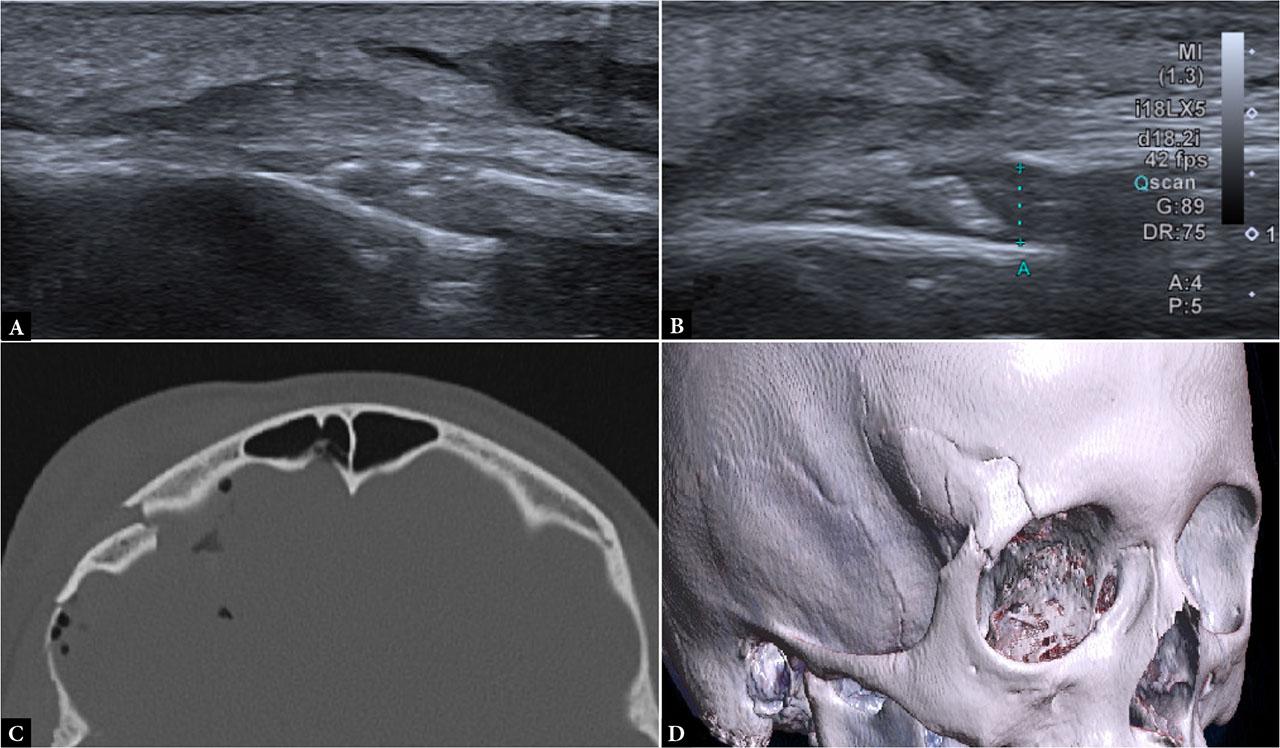

All patients were first clinically evaluated by a pediatric surgery resident or specialist in the emergency department. Based on surgical assessment, patients were referred to the radiology department, where ultrasound examinations were performed in a dedicated ultrasound room using a CANON Aplio i700 ultrasound machine, equipped with a high-frequency linear transducer (11–18 MHz). Children were positioned supine or, in cases of occipital trauma, in a prone or sitting position, accompanied by a caregiver, with gentle immobilization applied when necessary to minimize motion artifacts. The area of impact, hematoma, or maximal tenderness was systematically scanned in both longitudinal and transverse planes, with additional sweeps of adjacent and contralateral regions for comparison. In the absence of clear clinical signs of impact area, or problems with indicating the expected site of injury (non-verbal children), a broader portion of the skull was routinely examined. Particular attention was paid to differentiating fracture lines from normal cranial sutures at the affected site by tracing sutures to a fontanelle where possible or by comparing with symmetric contralateral structures. Major cranial sutures were assessed only at the affected site and adjacent collateral locations to distinguish normal suture lines from potential diastasis. ( Fig. 1, Fig. 2, Fig. 3, Fig. 4) No cases of sutural diastasis were identified in the cohort. All scans were performed by 15 radiology department physicians, either trained pediatric radiology residents or board-certified specialists. Interobserver variability was not formally evaluated.

Comminuted fracture of the frontal bone involving the superior and superolateral wall of the right orbit. A. Ultrasound examination showed a displaced fracture in the region of the right supraorbital arch, with (B) a 4-mm cortical invagination (calipers). C, D. CT examination confirmed a comminuted fracture of the superior and superolateral orbital wall